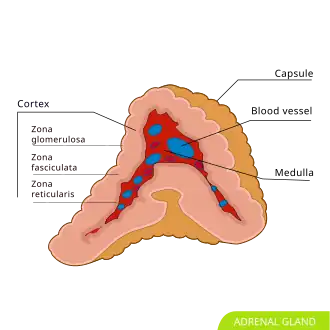

Adrenal gland; the medulla (center, red) is the origin of the pheochromocytoma.There is an adrenal gland, highlighted in yellow, on top of each of the kidneys.